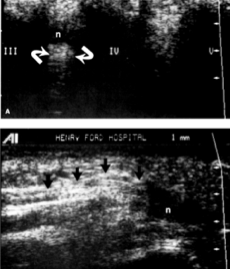

El médico generalmente puede diagnosticar este problema examinándole el pie. Se puede

tomar una radiografía del pie para descartar problemas óseos. Con una resonancia

magnética o una ecografía de alta resolución, se puede diagnosticar con éxito el neuroma de

Morton.